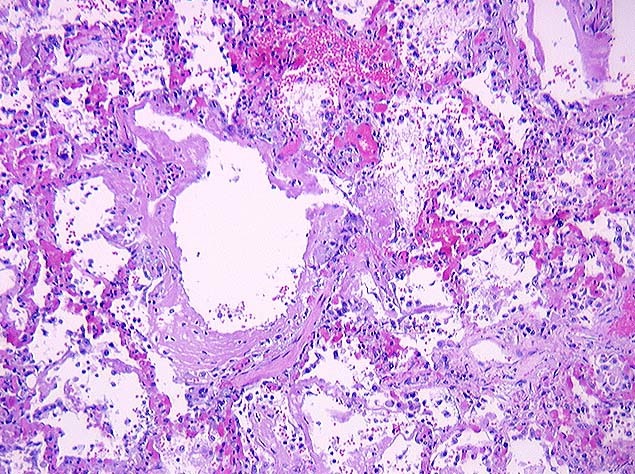

Acute, severe abdominal pain 6 weeks after LMP

(Vili + lots of blood = ectopic ruptured pregnancy)

Histology of an ectopic placenta just prior to rupture would reveal:

Two layers of vili, syncytiotrophoblast outside and cytotrophoblasts inside, minimal blood vessel

(Ectopic usually ruptures 6 weeks after LMP, so well within first trimester)